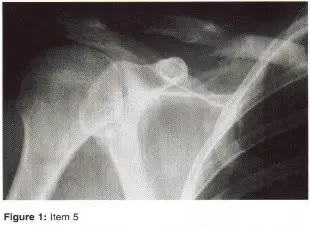

- مفصل الكتف: هو مفصل كروي حقي أيضاً، يُعرف بمرونته العالية على حساب استقراره. يتكون من رأس عظم العضد والتجويف الحقاني في لوح الكتف. تُعد إصابات الكفة المدورة (Rotator Cuff) وتمزقات الشفا (Labral Tears) شائعة، مما يؤدي إلى عدم استقرار الكتف أو الألم المزمن.

الأشعة السينية (X-rays): هي الخطوة الأولى في معظم حالات إصابات العظام والمفاصل. تُظهر صورًا للعظام وتُساعد في تشخيص الكسور (مثل كسور عظم الفخذ أو الترقوة)، والخلوع، وتشوهات العظام (مثل الجنف أو تشوهات النمو)، وتغيرات التهاب المفاصل (تآكل الغضروف، النتوءات العظمية). كما تُستخدم لتقييم التئام الكسور بعد العلاج.